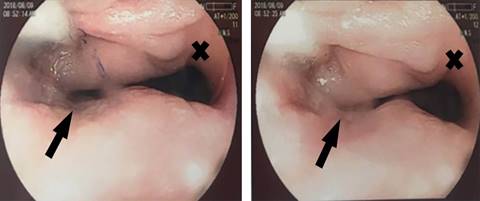

The preliminary clinical concern was about the possibility of esophageal compression due to lymph node metastases of breast cancer. This hypothesis was ruled out by the images of computed tomography (CT) with contrast showing a large diverticulum as a paravertebral expansive lesion on the right side at the cervicothoracic level. As some osteolytic and osteoblastic lesions due to breast cancer implants were detected at the bodies of T1 and T2, the suspicion of nerve root compression was later discarded by cervical nuclear magnetic resonance (MRI). Other concern was about a pouch carcinoma, but the upper gastrointestinal endoscopy (UGE) ruled out this complication, and showed the large saccular change at 12 cm from the upper dental arch, with discrete atrophy of the esophageal mucosa (Figure 1). During the UGE, a nasoenteric tube was placed in order to maintain a feeding pathway for the patient. With evidence of diverticulum and suspected bone metastasis, imaging exams were done for staging of neoplasm, including CT with contrast of the abdomen and pelvis that revealed a hypovascular lesion suggestive of liver metastasis. For more adequate diagnostic complementation of the esophageal diverticulum, an esophagography with barium was performed and confirmed the presence of a conspicuous ZD (Figure 2).

Figure 1: Upper gastrointestinal endoscopy study showing the esophageal lumen (X), and the opening of the Zenker’s diverticulum (arrow).